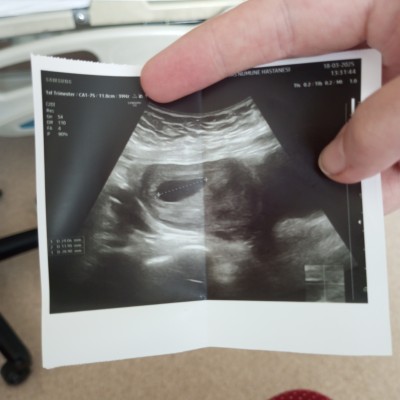

Kzlar 6+3 hamileyim bugün ultrasondan baktılar kesede bebek yok boş gebelik olabilir dediler sizce bosmu sonradan görünürmü

image